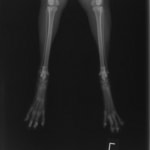

症例3:キルシュナーワイヤーのピンニングによる整復

ペルシャ猫 11ヶ月齢 雄

他院にて左大腿骨遠位の成長板骨折(salter-harrisⅠ型)が認められており、治療相談を目的として来院。当院にて、キルシュナーワイヤーを用いたピンニングにより骨折部位の整復を行いました。術後の経過は良好で、現在も経過観察中です。

術前レントゲン

術後レントゲン